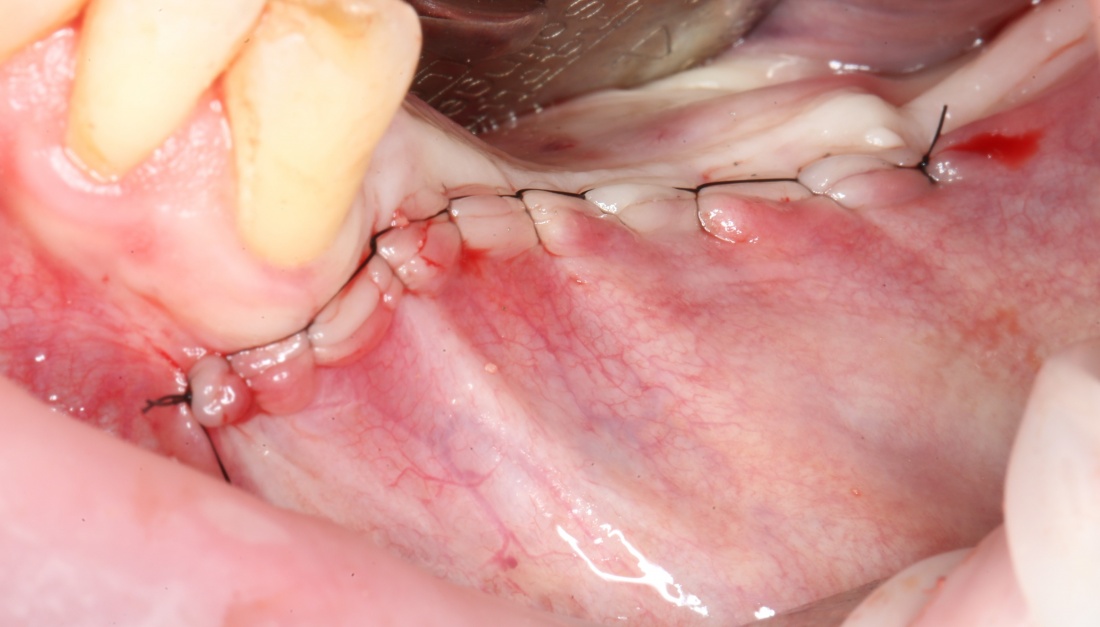

9. Наложение швов.

Я ни разу не испытывал каких-то проблем с ушиванием операционной раны. Как правило, её края сходятся достаточно легко без дополнительной периостотомии. Для наложения швов мы используем монофиламентные нерезорбируемые нити диаметром 5-0 (Resolone, Prolene, Полипропилен и др.).

Обычно, через день после операции рана выглядит вот таким образом:

Швы можно снять на 10-14 день.